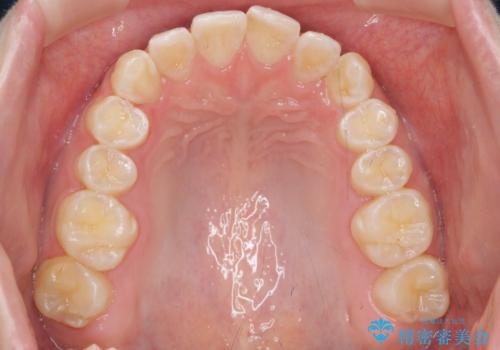

前歯のねじれを治したい マウスピース矯正治療

- 前歯のねじれを改善し、きれいな歯並びにしたい!と矯正治療を希望され来院されました。

マウスピース矯正システム、インビザラインのシミュレーションを用いて最終的な歯の位置をしっかりと確認したのち、きれいな歯並びとなるようマウスピース矯正治療を開始します。

ねじれとともに突き出たように見えていた前歯も見た目が大きく改善し、喜んでいただくことができました。